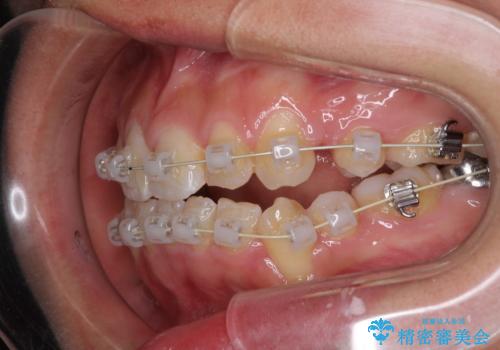

前歯が八重歯でガタガタ ワイヤーによる抜歯矯正

- 前歯のガタガタを主訴に来院されました。

前歯の重度のガタガタで、八重歯もある状態でした。

また右下の乳歯が残っており、永久歯が1本足りませんでした。

上顎両側と左下の前から4番目の歯と、右下の乳歯を抜歯して矯正することとなりました。

乳歯を抜歯することにより、通常よりは治療期間を要してしまいましが、前歯のガタガタもなくなりきれいな歯並びになったと喜んでいただけました。